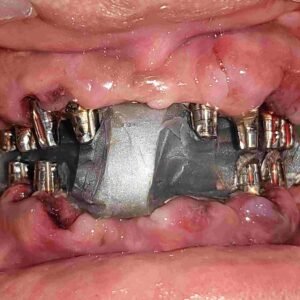

1002 Basal Full Mouth Implants Case Rubeena 2

1002 basal implant full mouth case rub 4